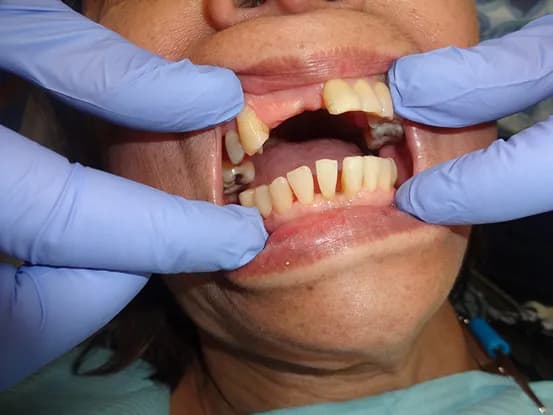

Case 11

62 year old female with overbite and multiple worned and discolored teeth and wanted a dental cosmetic makeover. 3 quadrants osseous surgery, crown lengthening and 20 units of E-Max restorations performed to restore smile to a more youthful look.